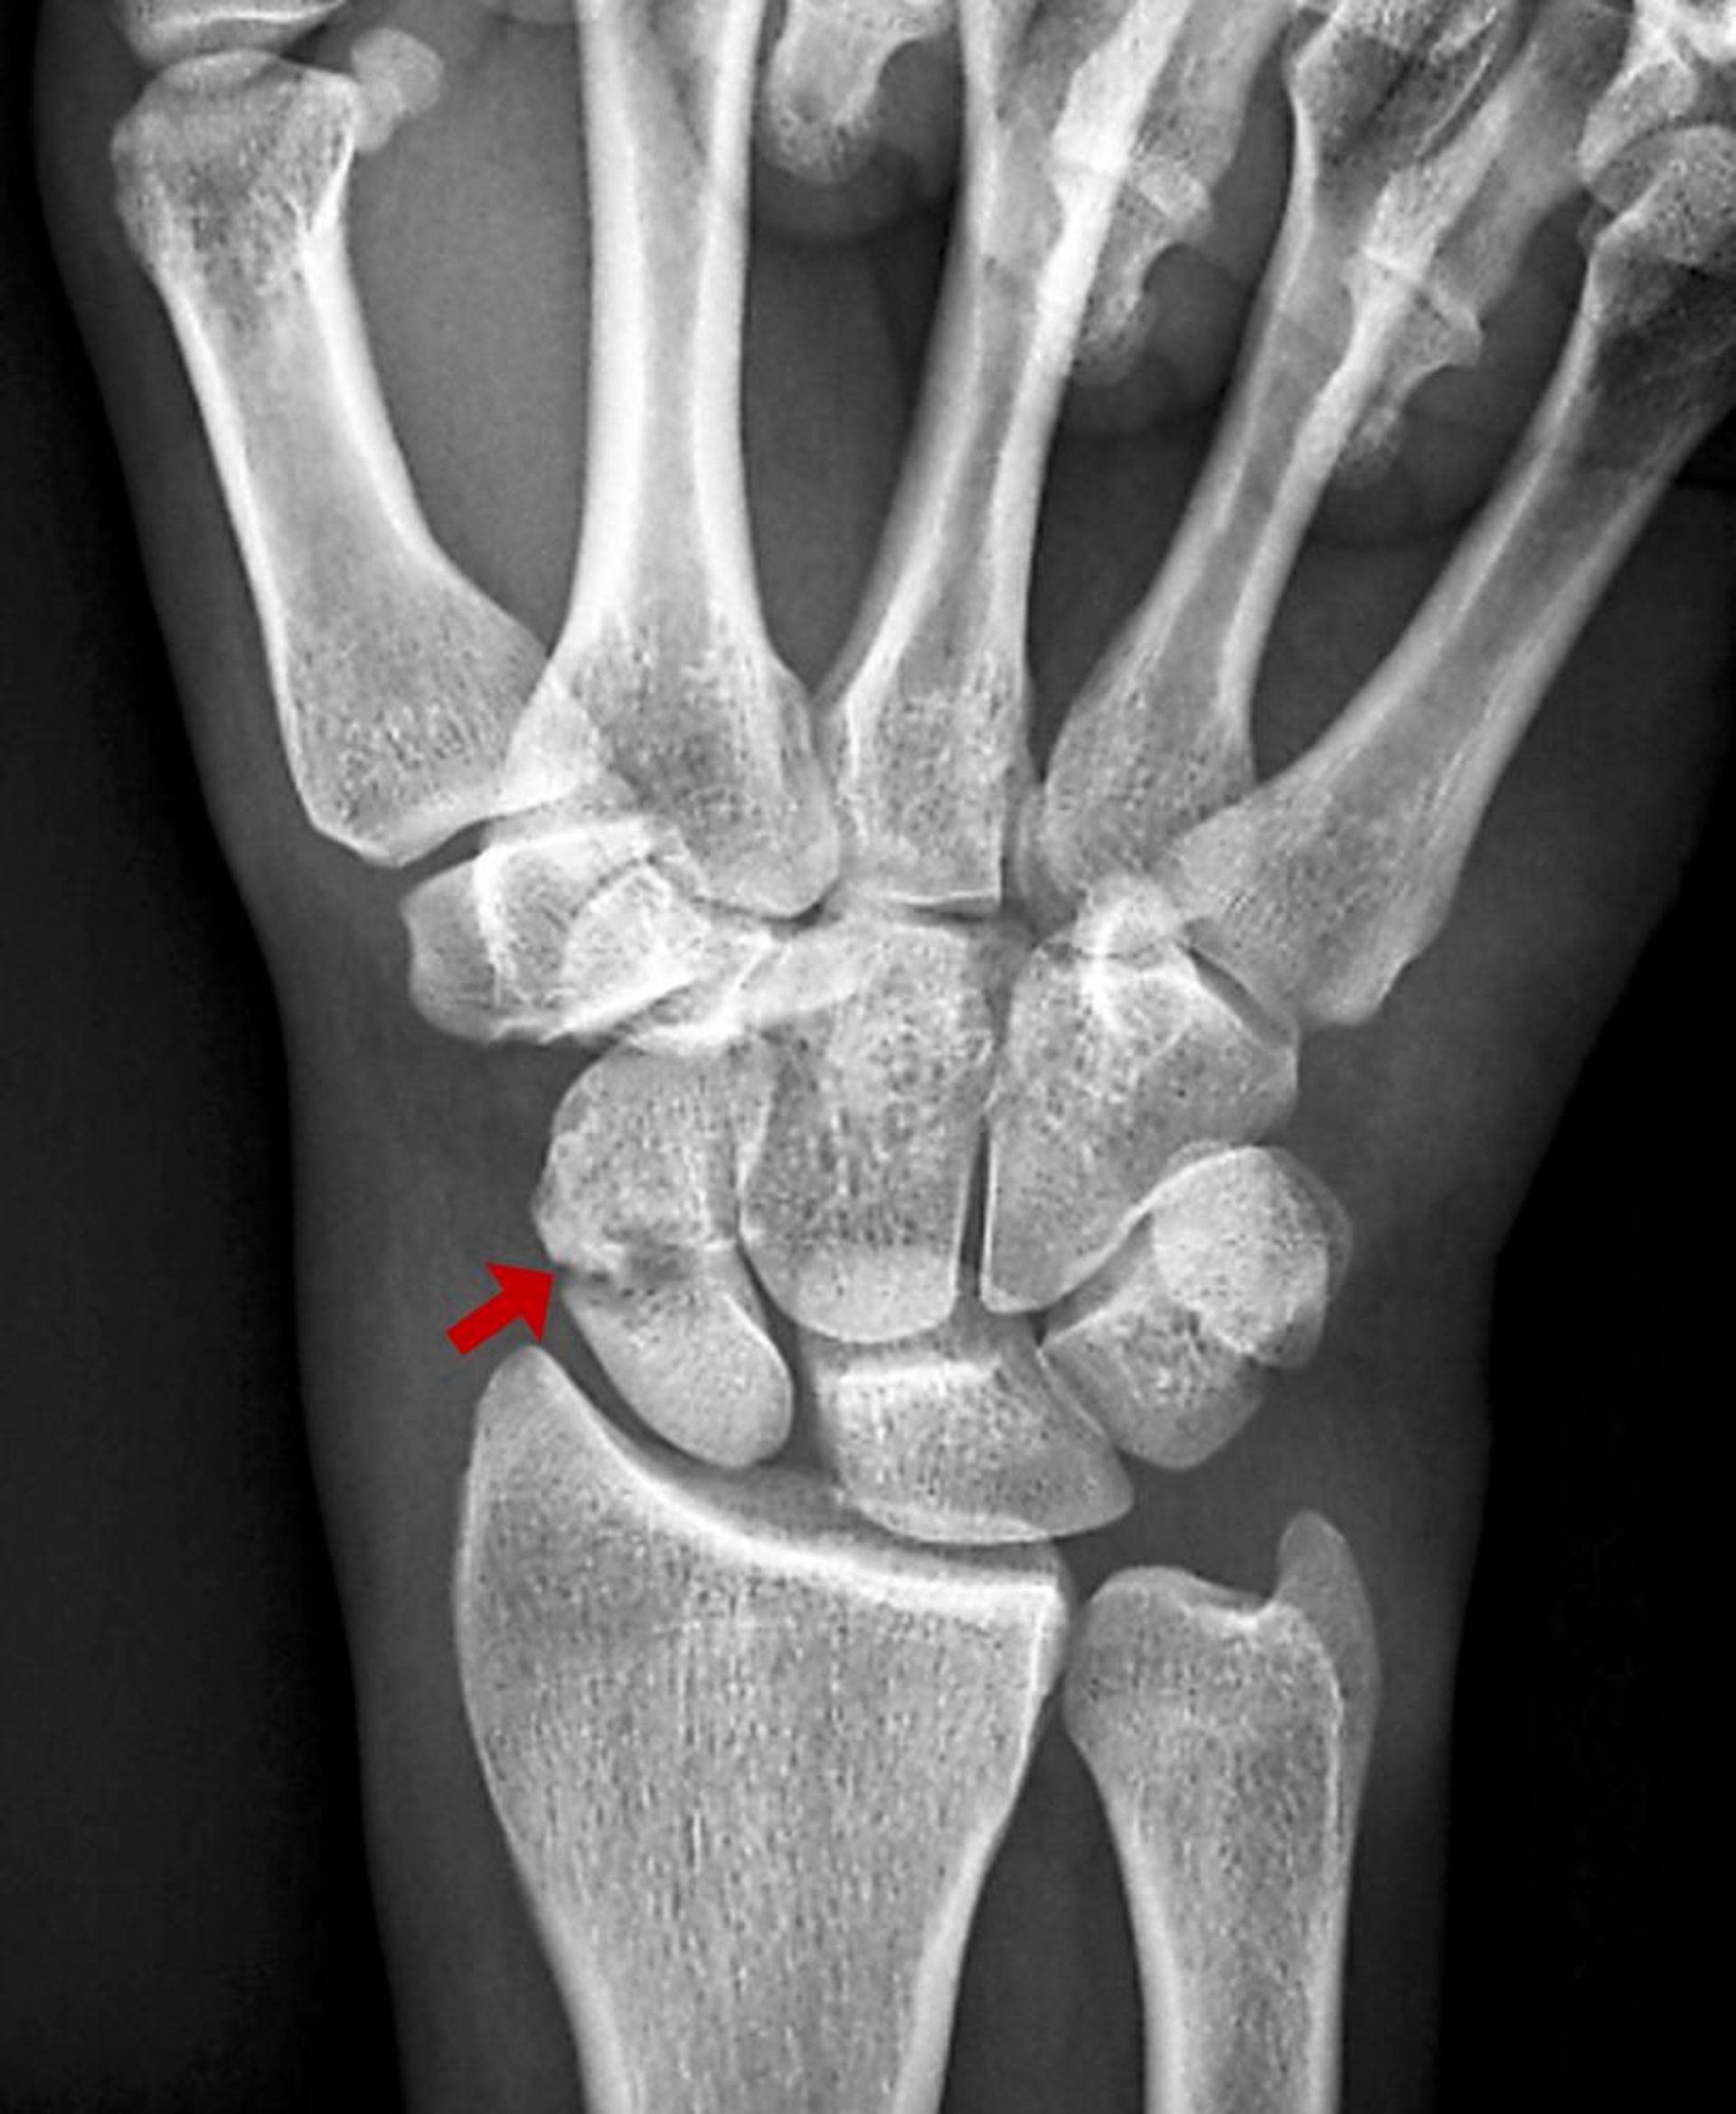

Esta fractura de escafoides es visible como una imagen radiolúcida en la radiografía simple.